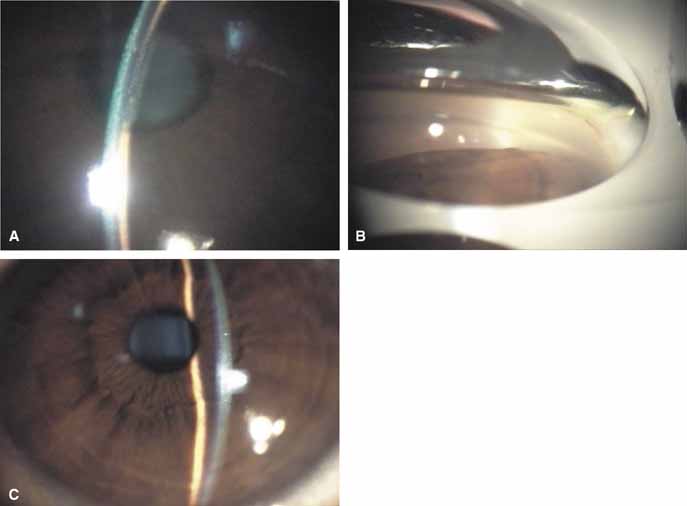

The possible association between retinitis pigmentosa and glaucoma dates back to 1862.11 Over the past century the reported glaucoma incidence has varied between 2.98% to 10% of all cases of retinitis pigmentosa.12,13 Of concern in all previous reports is the accuracy of the diagnosis of retinitis pigmentosa itself, a hereditary disease with diverse manifestations. Retinitis pigmentosa-like syndromes may mimic glaucomatous field loss, and the pattern of advancement of visual field loss in true retinitis pigmentosa may parallel that of typical open-angle glaucoma. Patients with undiagnosed retinitis pigmentosa may have subtle fundus findings, especially those with the sine pigmento form (Fig. 1). A clue to diagnosis is the disproportionate peripheral field loss in comparison to the degree of optic nerve cupping and rim pallor. Patients with atypical field loss and minimal optic nerve cupping should have an electroretinogram to exclude unsuspected retinitis pigmentosa.

Active retinal involvement in acute toxoplasmosis may be associated with an acute elevation of intraocular pressure, sometimes producing corneal edema. When the cornea is cleared with topical glycerin, the angle is found to be open and a minimal anterior chamber reaction is present. The mechanism of the glaucoma is believed to be immune complex (antigen–antibody) deposition in the trabecular meshwork, rather than obstruction by cellular debris.21 The elevated pressure responds well to timolol or acetazolamide and does not require topical corticosteroids. Systemic treatment of the active retinitis should follow only if the optic nerve (positive Marcus Gunn), macular center, or peripapillary retina is involved. This unique entity will be missed if a fundus examination is not performed in all cases of hypertensive uveitis (Fig. 2).

The majority of cases of ghost cell glaucoma occur following vitrectomy for diabetic retinopathy, vitreous hemorrhage due to trauma, or vitreous hemorrhage following anterior segment surgery (i.e., cataract extraction or corneal transplant). Although studies suggest that a disruption of the anterior hyaloid face may be a necessary precedent, ghost cell glaucoma probably can occur with an intact hyaloid if a sufficient quantity of vitreous blood is present.27 The clinical presentation includes acute pressure elevation, corneal edema, and lack of keratic precipitates. Minute tan cells (ghost cells) may layer out, producing a pseudohypopyon or, if admixed with blood, a “candy-striped” hypopyon. (Fig. 3) Intraocular pressure elevations after diabetic vitrectomy raise concerns regarding concomitant neovascular glaucoma. However, neovascular glaucoma rarely develops in the immediate postvitrectomy period, unless some anterior segment neovascularization was present preoperatively. Late-onset pressure elevations (> 6 to 8 weeks out) in a postvitrectomized diabetic eye usually signal neovascular glaucoma.